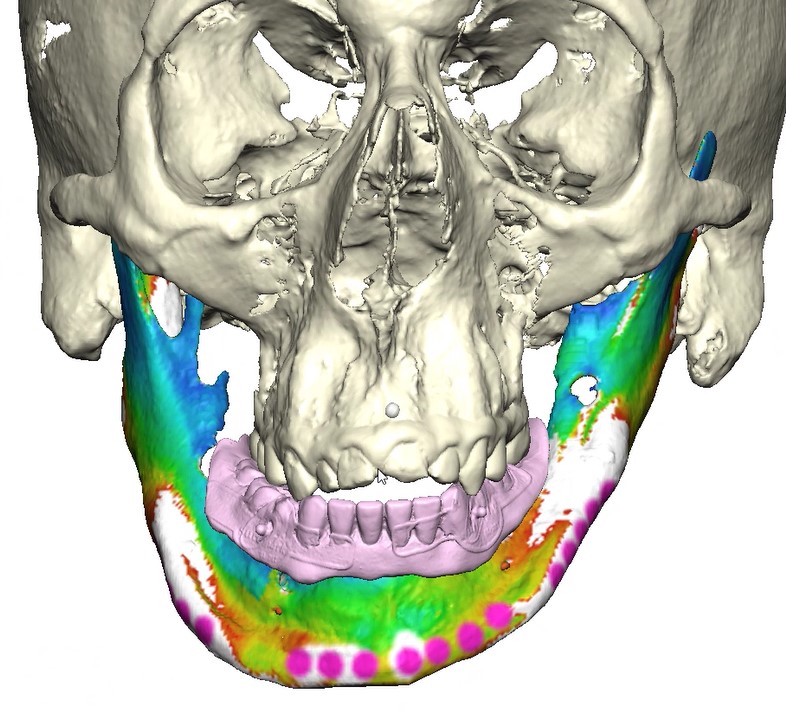

Records for this patient were collected using a dual-scan CBCT and intraoral scanning. A surgical planning session was completed with KLS Martin for the fabrication of a CAD-CAM subperiosteal implant system with immediate loading of a mandibular prototype (Figs 2-5).

A 3D-printed mandibular model with the subperiosteal system and prototype in place was also fabricated (Figs 6 and 7).

The custom titanium framework was trial seated and adapted accurately.

• Stereophotography scans of the cast were performed with the prototype in place and after removal with ICam4D scan bodies using Trios 4 Wireless Pod (3Shape) (Figs 12-14).